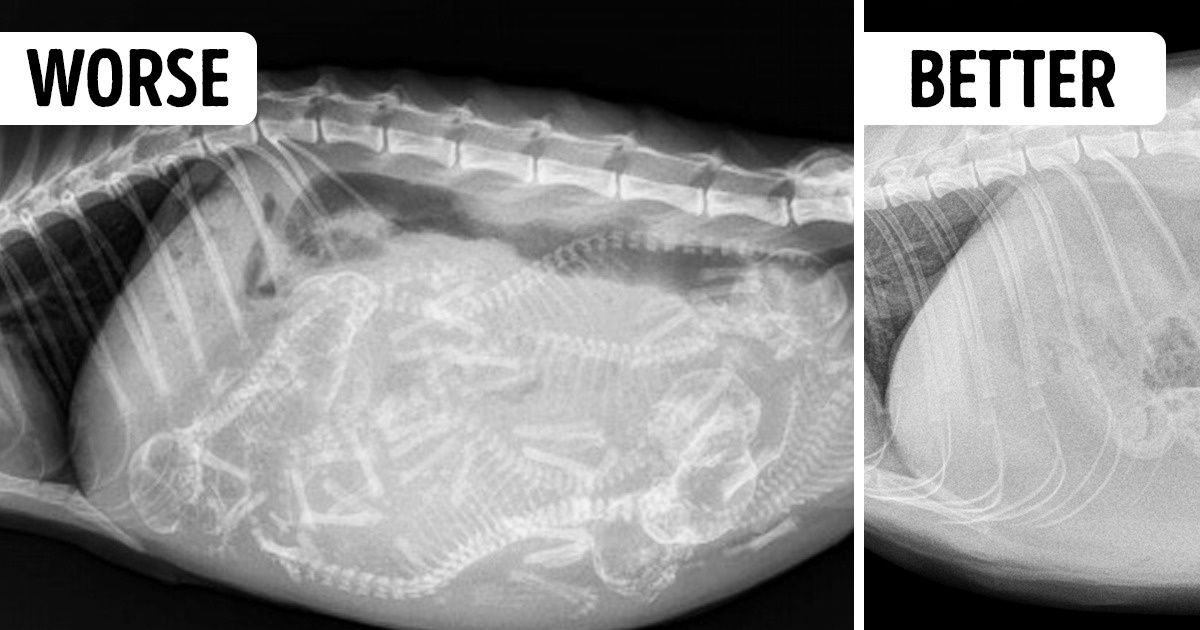

Upper photo: an X-ray image of a pregnant cat. Lower photo: an X-ray image of a spayed cat.

In most cases, these procedures have a positive impact on a cat’s health. They reduce the risk of mammary tumors in female cats and testicular tumors in male cats. Moreover, neutered cats aren’t prone to aggression or running away from home.